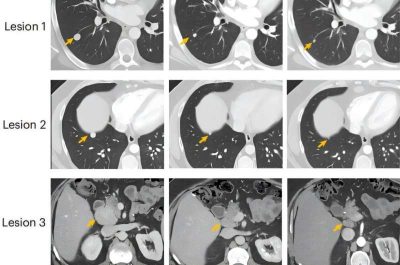

Cancro al fegato-immagine: